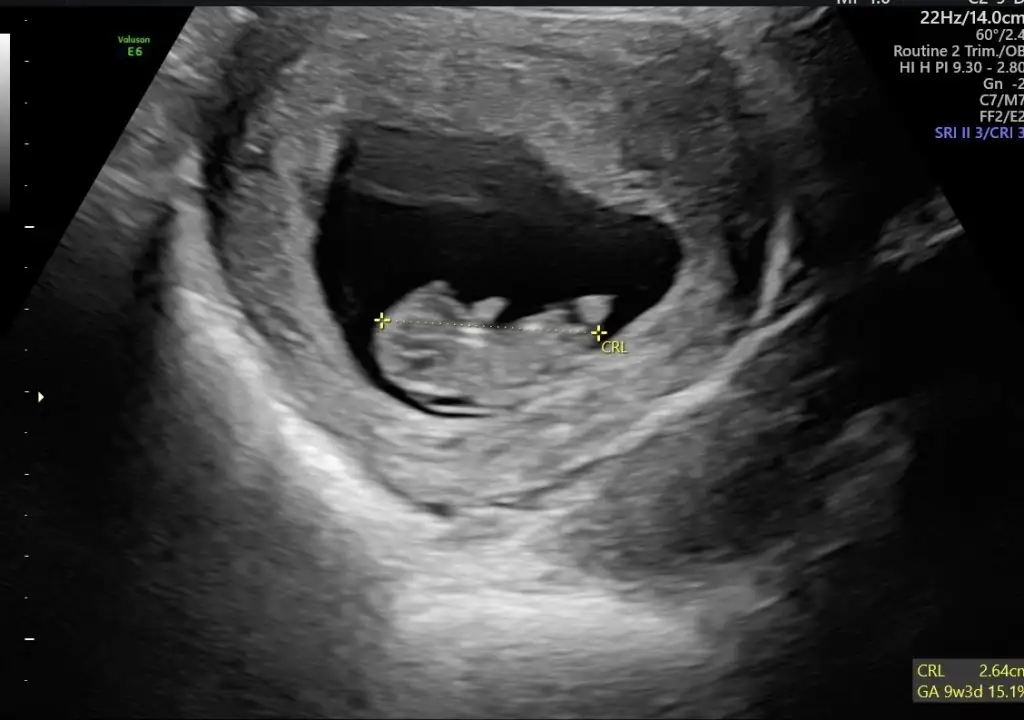

8 haftalık karından .Bana da tahminde bulunur musunuz 😊

Eklentiler

• C3184BD6-722B-4266-82B7-9E0785459309.webp

C3184BD6-722B-4266-82B7-9E0785459309.webp

20,7 KB · Görüntüleme: 80